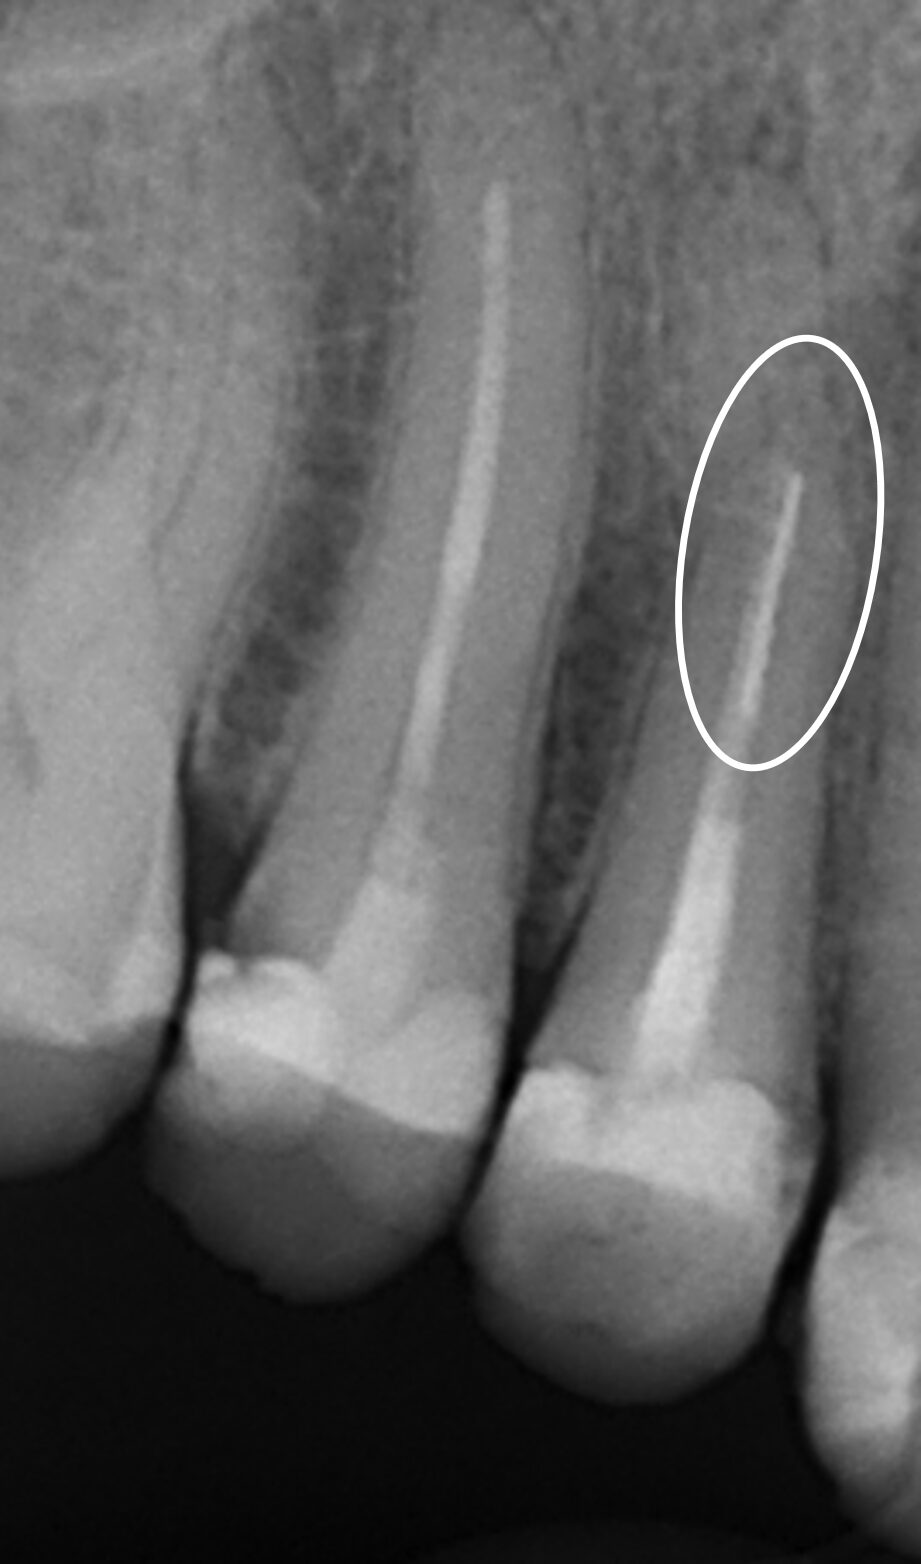

Hugo Case Post xRay

Post-OP X-Ray

The fractured file was

successfully removed.

EC Loop Hugo Case

Yellow Lasso 0.12mm

Captured file.